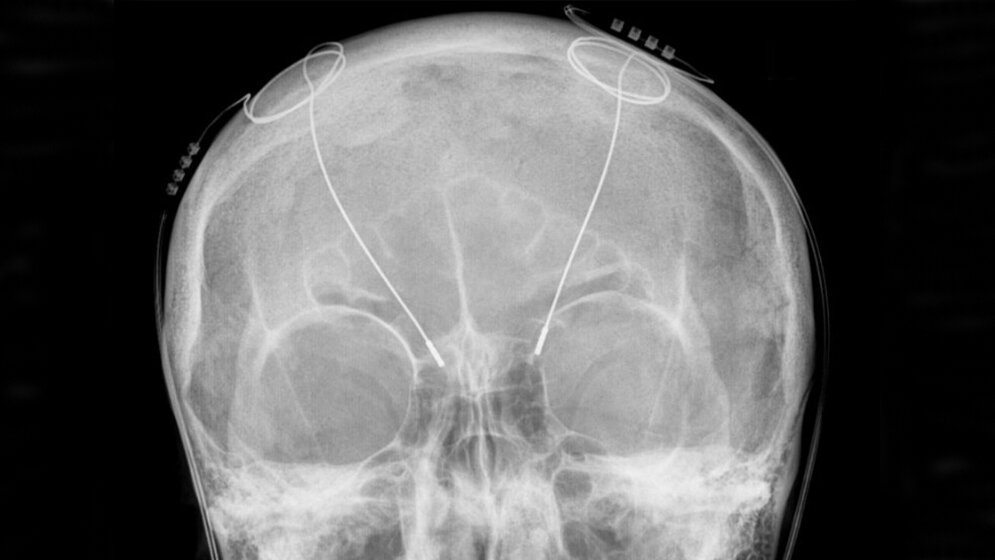

„Als Faustregel gilt, dass die frühe Diagnose und Differenzialdiagnose des Parkinson-Syndroms in erster Linie auf der kompetenten neurologischen Anamnese und Untersuchung basieren“, so Prof. Heinz Reichmann aus Dresden, Mitglied der Leitlinien-Steuergruppe. In einigen unklaren Fällen können bildgebende Zusatzuntersuchungen jedoch über die rein klinische Untersuchung hinaus hilfreich sein, um so früh wie möglich eine korrekte Diagnose stellen zu können. So sollte zum Ausschluss symptomatischer Ursachen beim Parkinson-Syndrom grundsätzlich eine zerebrale Bildgebung, also craniale Computertomographie (cCT) oder craniale konventionelle strukturelle Magnetresonanztomographie (MRT) zur Differenzialdiagnose beitragen.

Für Patienten mit fortgeschrittenem IPS und motorischen Komplikationen stehen neue invasive Therapien zur Verfügung, die nur bei geeigneten Patienten eingesetzt werden sollten. Die Experten heben hier die gut untersuchte Tiefe Hirnstimulation hervor. Die Tiefe Hirnstimulation kann schon in den ersten drei Jahren nach Beginn von Fluktuationen oder Dyskinesien bei geeigneten Patienten angeboten werden, wie die EARLYSTIM-Studie gezeigt hat. Bei der Pumpenbehandlung mit der intrajejunalen Levodopa/Carbidopa-Infusion liegen mittlerweile Daten vor, die eine gute Wirksamkeit belegen. Die subkutane Apomorphin-Infusion ist ein Verfahren, das derzeit geprüft wird.